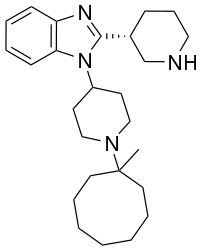

Benzimidazoles

Structures

| Benzimidazoles | ||||

|---|---|---|---|---|

|

|

|

|

|